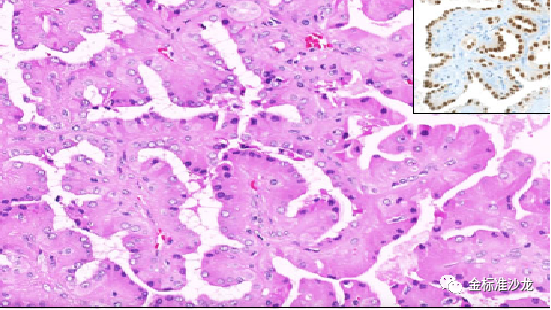

其中一种肿瘤是双相鳞状腺泡样RCC,需要与1pRCC鉴别诊断(图4)低倍镜下见肿瘤境界清楚,肿瘤呈乳头状、腺泡状及实性生长,乳头轴心周围瘤细胞的细胞核位于基底部,具有少量胞浆,高倍镜下观察到腺泡状结构由两类细胞组成,外层由胞浆较少的小细胞,包绕腺泡中心胞浆较丰富的大细胞。小细胞形态类似经典的Ⅰ型乳头状肾细胞癌肿瘤细胞特征,可见小核仁,大细胞胞浆丰富,嗜酸性,核呈空泡状,类似“鳞样细胞”。免疫组化上,大细胞表达cyclinD1CD57。暂时,该肿瘤仍属于pRCC谱系内,不是作为一个独立的实体。因其常伴有经典的1型pRCC区域, 717染色体获得,以及MET基因的突变,表明它们可能属于1pRCC的延续目前大多数报告患者无病生存,但据报道有人死于疾病。但报道病例的数量(<65)仍不足以评估这种罕见亚型的临床病程。

图4 肿瘤由两类细胞组成,外层由胞浆较少的小细胞,包绕腺泡中心胞浆较丰富的鳞样的大细胞。大细胞免疫组化CyclinD1阳性